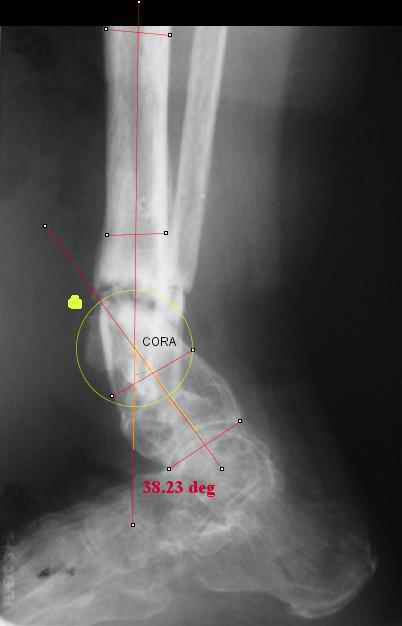

I played with your image using some orthopedic software we have been developing for digital

image analysis.

What you see marked up is the intercept of two mid-line tool centre lines, used to define the CORA. An angle tool gives the angular deformity and a circle tool is applied to show that a correction around the CORA through the old # will restore alignment without much translation.

Maybe my "embedded software" is obsolete but it hints me to place hinges at the yellow point - this must result with alignment and some lengthening without translation. What do you think?

I think that if you locate the hinge at that site and then you rotate the foot about this point with out distraction you will be perfectly lined up. If you distract in the axis of the proximal tibia then rotate, it should still work (the hinge should still be located in the mid tibial axis). But, if you distract out of that axis then you will get translation. Does that make sense?

I looked at your image. I presume your yellow marker is the hinge axis? I think this should be at the CORA.